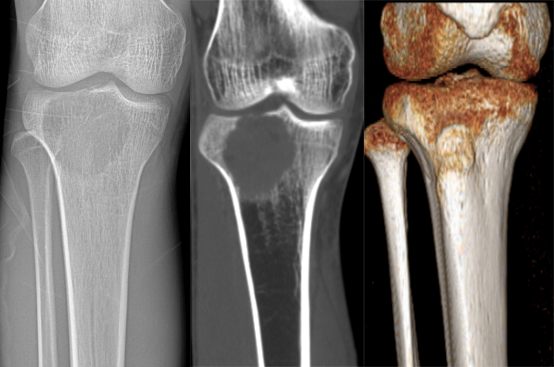

CASE 1

男性,23 岁,主诉:右小腿上段疼痛伴右膝关节肿胀 2 月余 医学百科网 | YxBaike.Com

免疫组化结果:右胫骨肿瘤,骨巨细胞瘤。 医学百科网 | YxBaike.Com